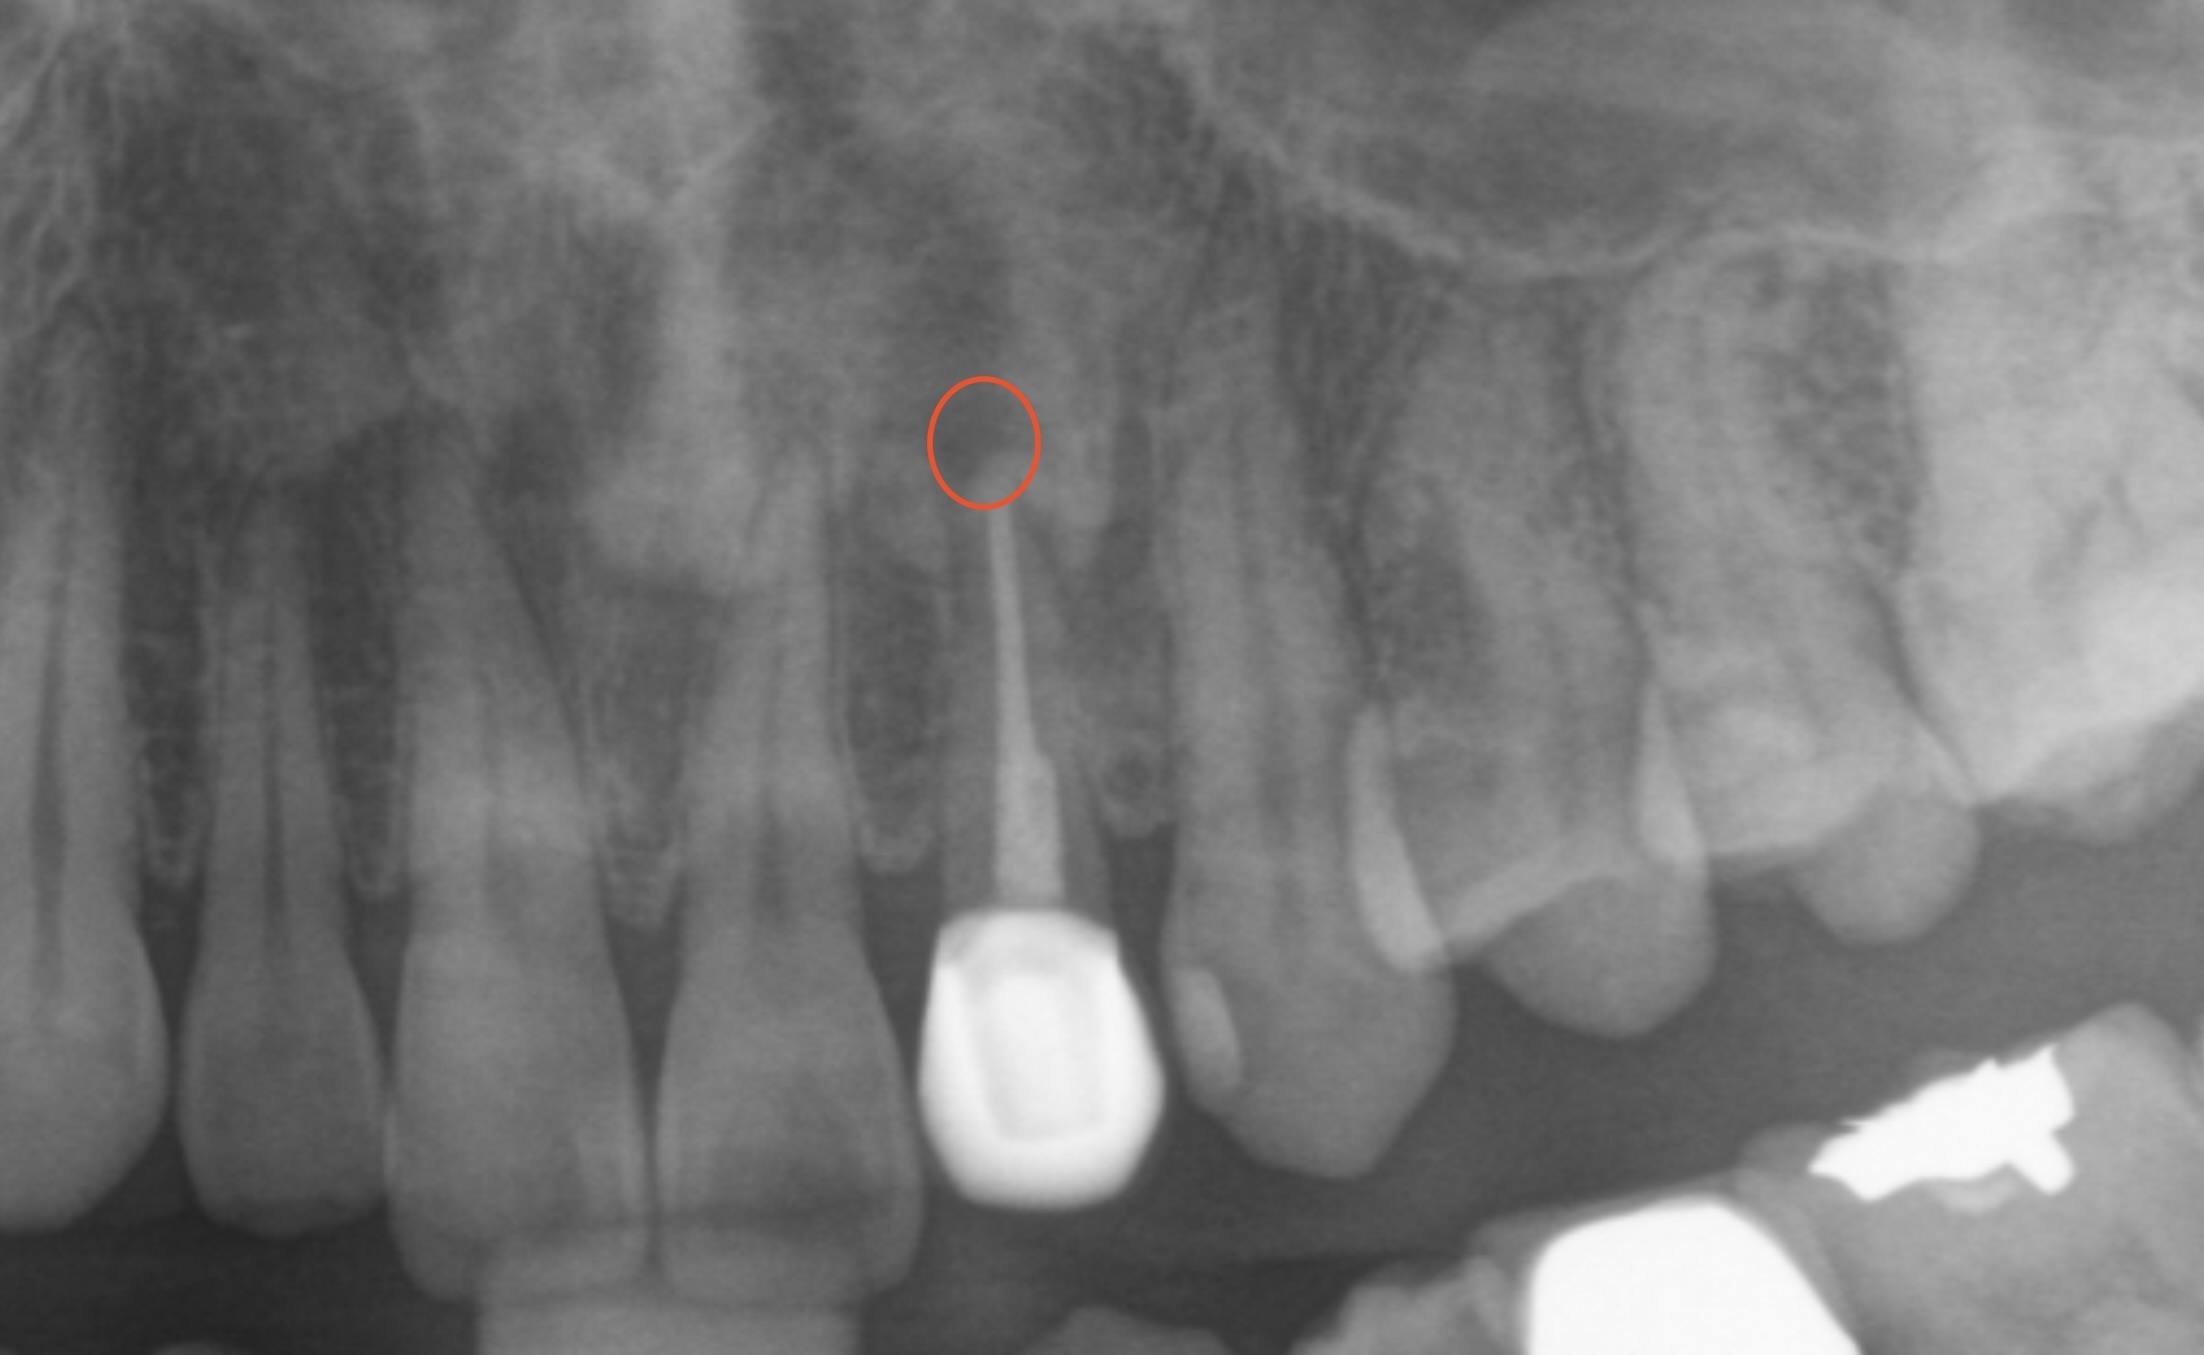

レントゲン像を確認すると、根っこの先に膿が溜まっているような像も見えましたので

根っこの先の膿の像も8ヶ月ほど経って

半分以下に縮小、改善してきているのが確認できました(レントゲン像赤丸部)